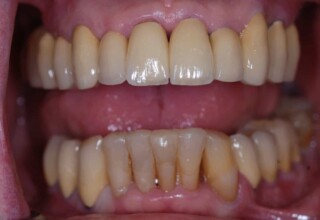

Extensive case with crowns in almost all teeth

Extensive case with crowns in almost all teeth due to extensive wear, old restorations, posterior root canals and aesthetic concerns. Patient (60years old) presented with intense bruxism which he never had treated. Consequently, he obtained very deep cervical abrasions which jeopardized tooth integrity. Restorations (fillings) were executed mainly with adhesive resinous materials and three custom cast post and cores. Temporary crowns were placed to evaluate the desired size, shape and position of the teeth before permanent crown fabrication.

Initial smile

Final Smile